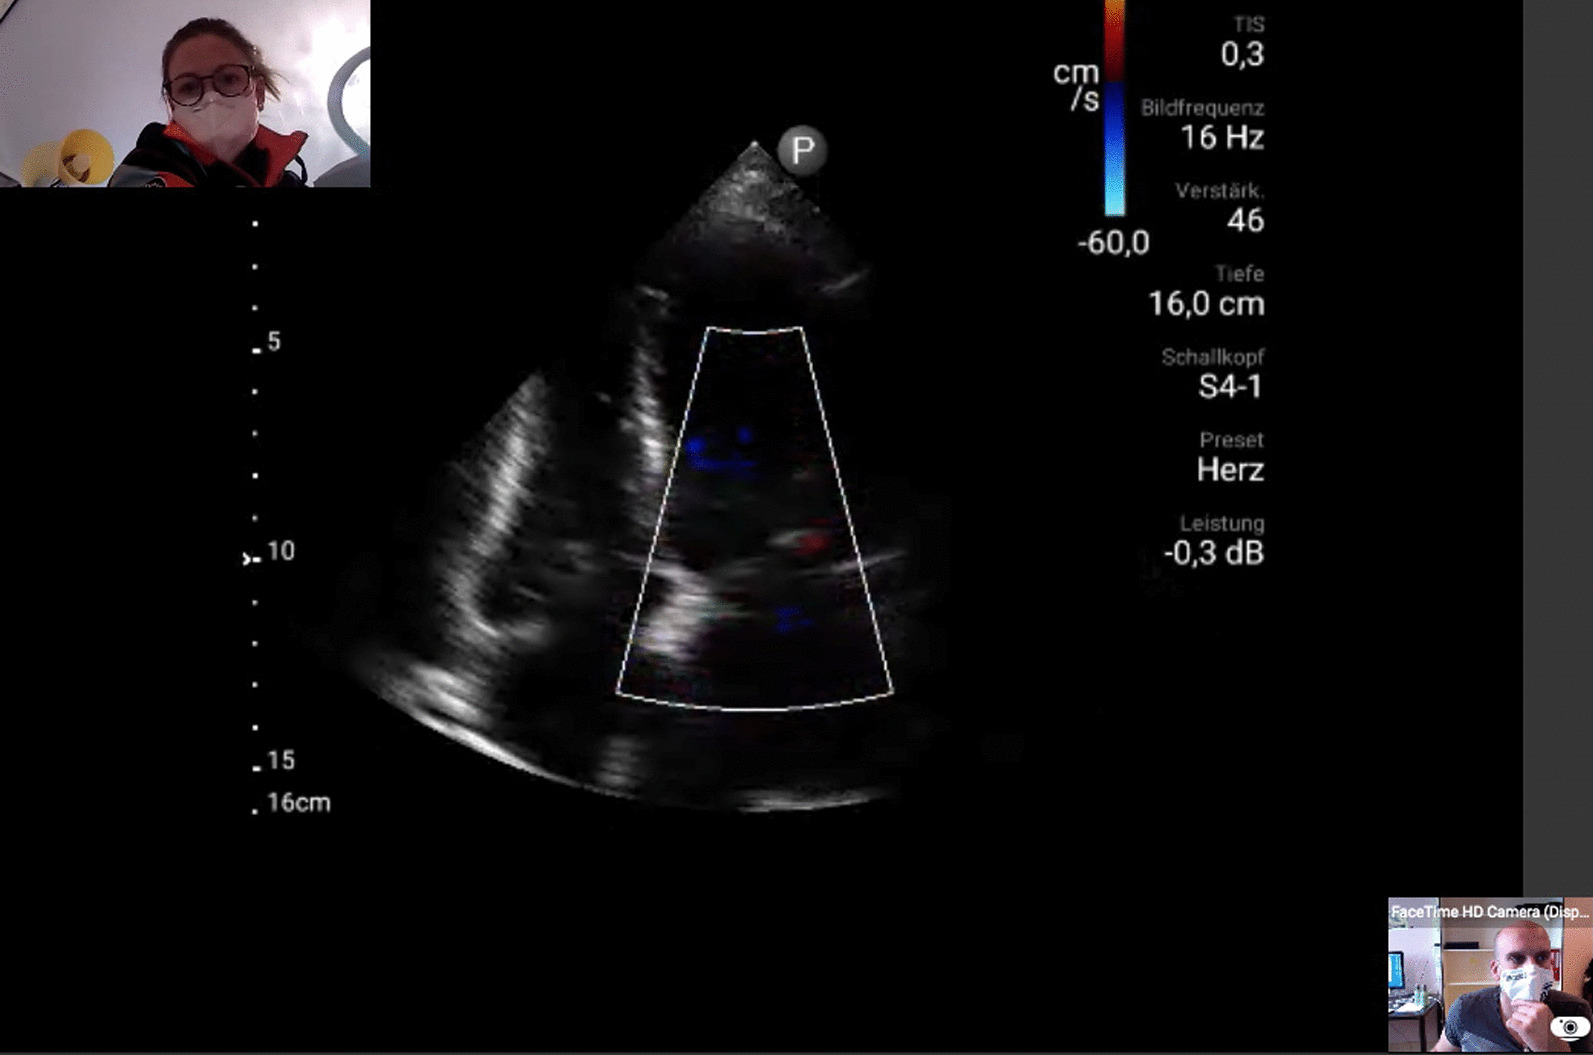

Background: Although prehospital point-of-care ultrasound (POCUS) is gaining in importance, its rapid interpretation remains challenging in prehospital emergency situations. The technical development of remote real-time supervision potentially offers the possibility to support emergency medicine providers during prehospital emergency ultrasound. The aim of this study was to assess the feasibility of live data transmission and supervision of prehospital POCUS in an urban environment and so to improve patients' safety.

Methods: Emergency doctors with moderate ultrasound experience performed prehospital POCUS in emergency cases (n = 24) such as trauma, acute dyspnea or cardiac shock using the portable ultrasound device Lumify™. The ultrasound examination was remotely transmitted to an emergency ultrasound expert in the clinic for real-time supervision via a secure video and audio connection. Technical feasibility as well as quality of communication and live stream were analysed.

Results: Prehospital POCUS with remote real-time supervision was successfully performed in 17 patients (71%). In 3 cases, the expert was not available on time and in 1 case remote data transmission was not possible due to connection problems. In 3 cases tele-supervision was restricted to video only and no verbal communication was possible via the device itself due to power saving mode of the tablet.

Conclusion: Remote real-time supervision of prehospital POCUS in an urban environment is feasible most of the time with excellent image and communication quality.